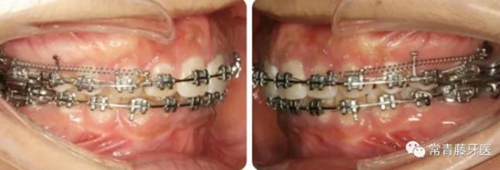

A67、B67之間植入微種植釘整體內(nèi)收上牙列,下頜配合多用途弓整平牙列改善覆合。

繼續(xù)內(nèi)收上牙列,此時下頜spee曲線基本整平。